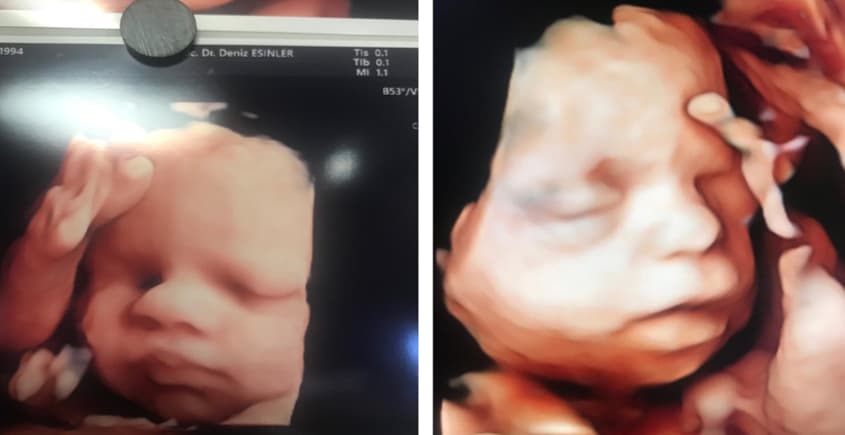

Gebeliğin 18-23. haftaları arasında yapılan, bebeğin tüm organlarının (beyin, kalp, böbrekler, eller, ayaklar vb.) detaylı olarak incelendiği radyolojik değerlendirmedir.

- Yüz profili, dudak ve damak yapısı